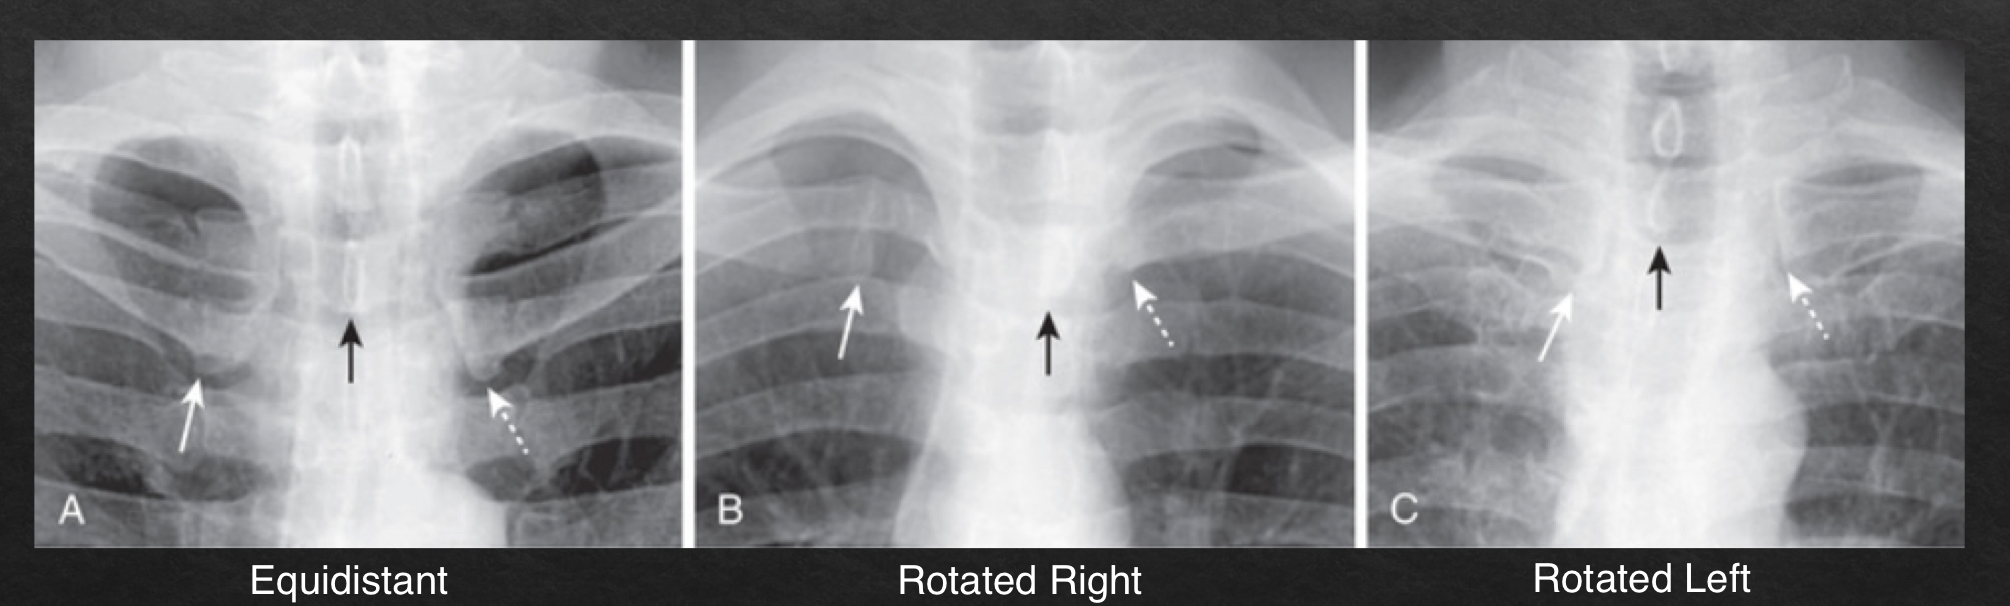

rotation

adequate rotation: spinous processes are equidistant btwn the medial ends of the clavicle

severe rotation findings

trachea appears shifted from midline (black arrow)

left lung appears much larger, right lung appears smaller

heart contour appears changed

left hemidiaphragm appears raised (white arrow)